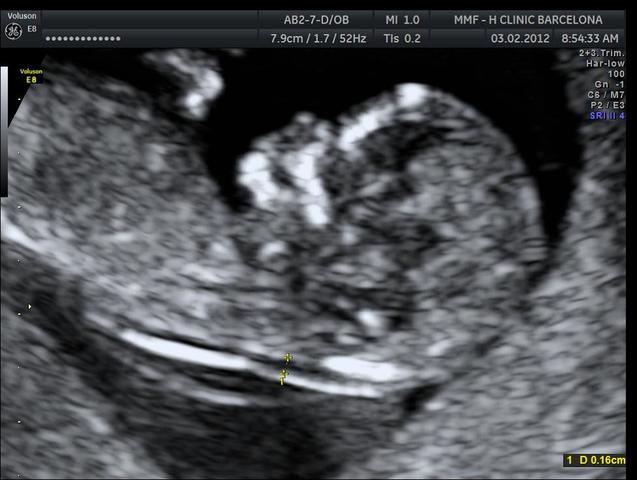

• PLIEGUE NUCAL

PLIEGUE NUCAL

Entre las semanas 11 y 14 es muy importante, además de la revisión sistemática, medir el PLIEGUE NUCAL, para descartar enfermedades cromosómicas, como el SINDROME DOWN